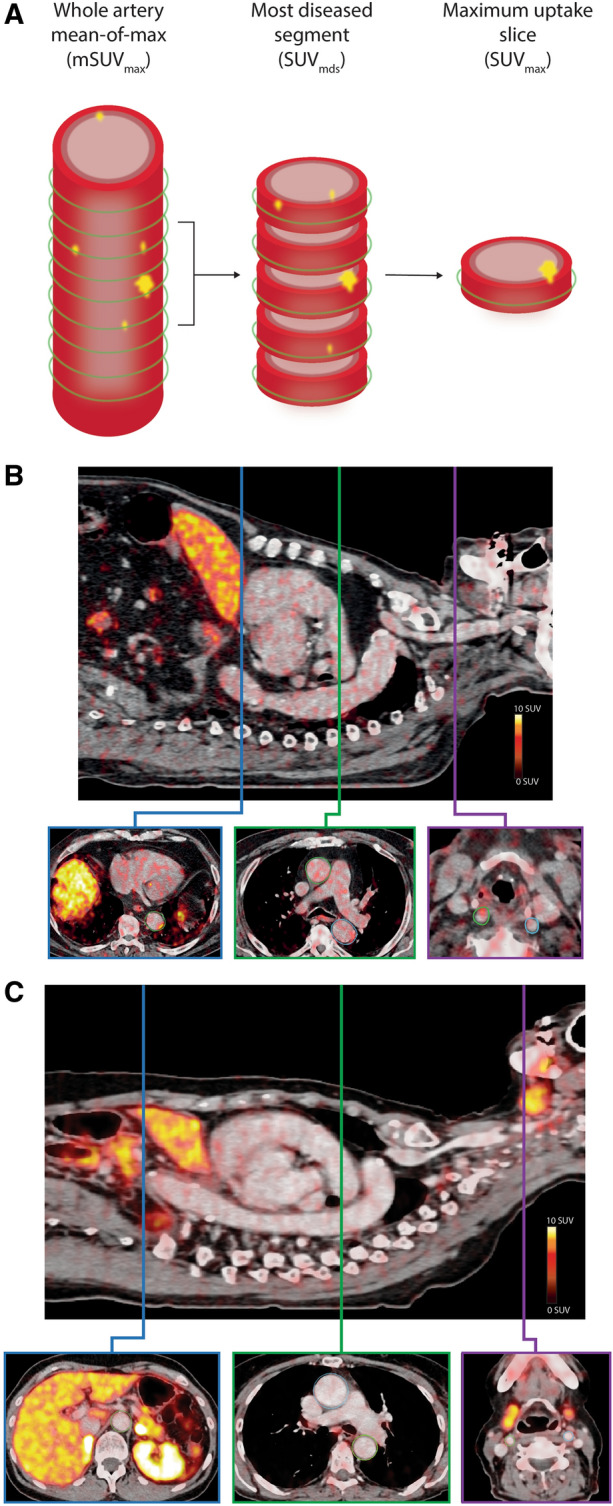

All PET/CT scans were analyzed using the Osirix MD imaging software platform ver. 11.0 (Pixmeo, Bernex, Switzerland). ROI’s were drawn on axial slices of the aorta and the carotid arteries. ROI’s of the aorta were drawn on both the ascending and descending portions of the aorta. ROI’s were drawn from 1 slice cranial to the aortic valve to the branching of the right renal artery of the descending aorta. In the carotids, ROI’s were drawn from 5 slices cranial to the carotid bifurcation, on the internal carotid artery, and downward to the aorta or subclavian artery. Standardized uptake values (SUV) were measured from each ROI. To account for background [64Cu]Cu-DOTATATE uptake, SUV values were divided with a background SUV value measured as the mean of 4 adjacent slices in the right atrium, to allow for calculation of target-to-background (TBR) values. [64Cu]Cu-DOTATATE TBR and SUV uptake values are reported as whole-artery maximum (SUVmax and TBRmax) and mean of max (mSUVmax and mTBRmax), where max values from all slices were averaged. Also, a most-diseased segment (SUVmds and TBRmds) of the artery approach, where the slice with the maximum SUV or TBR together with the 4 adjacent slices (2 on each side) was averaged, was also calculated and reported (Figure 2A). A representative example of the ROI’s drawn are shown in Figure 2B and C.

Figure 2.

Vascular [64Cu]Cu-DOTATATE image analysis and uptake quantification. (A) Schematic illustration of an index vessel and measurement method of the 3 different uptake metrics. Green circle indicates region of interest placement. Examples of region of interest demarcation of the vessel wall shown on fused PET/CT images of a patient in the known CVD group (B) with vascular wall uptake of [64Cu]Cu-DOTATATE and a patient in the control group (C) with little [64Cu]Cu-DOTATATE uptake. Top images of both (B) and (C) are showing a sagittal slice for reference. Bottom images shows axial plane slices with drawn regions of interest of the ascending and descending aorta (blue and green boxes) and the carotid arteries (purple box)